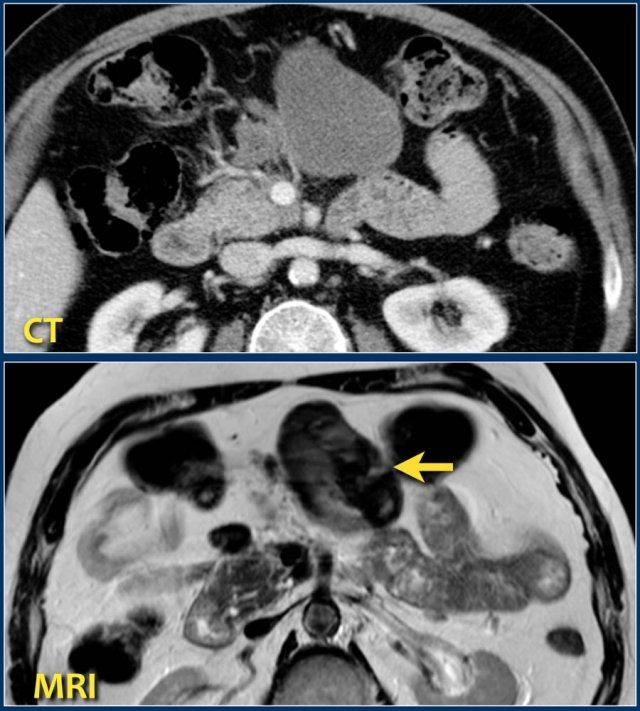

Các dấu hiệu bao gồm:

- Tụy ngấm thuốc bình thường toàn bộ.

- Các ổ dịch quanh tụy lan rộng, có tỷ trọng dạng lỏng và không lỏng trên CT.

- Có ít nhất hai ổ dịch, nhưng không có hoại tử nhu mô tụy (CTSI: 4).

- Vào ngày thứ 18, các ổ dịch quanh tụy mở rộng và xuất hiện thành không hoàn toàn.

Vào ngày thứ 5, ổ dịch này có thể được chẩn đoán là ổ hoại tử cấp tính có khả năng cao.

Vào ngày thứ 18, thành chưa hoàn toàn, nhưng có thể dự đoán rằng trong vài ngày tới đây sẽ trở thành ổ hoại tử được bao bọc với thành hoàn chỉnh.

Khi các ổ dịch quanh tụy tồn tại dai dẳng hoặc tăng kích thước, thường là do sự hiện diện của hoại tử mỡ.

Do mỡ không ngấm thuốc trên CT, việc chẩn đoán hoại tử mỡ có thể gặp khó khăn.

Hoại tử có thể được chẩn đoán bằng MRI, tuy nhiên chỉ nên thực hiện khi có ý nghĩa lâm sàng trực tiếp.